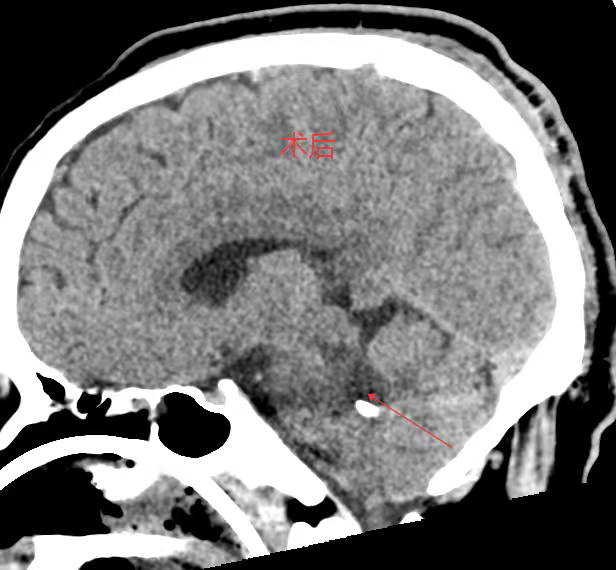

考虑到患者年轻、基础状况尚可,且出血部位深、传统开颅手术创伤大、风险高,医生团队决定采用脑立体定向仪引导下的微创穿刺血肿碎吸术。

主刀医生龙青山介绍,“我们利用立体定向系统,将穿刺误差控制在2毫米以内,仅需一个约3厘米的小切口,通过直径不足1厘米的骨孔置入穿刺管,直接进入血肿腔。”

手术过程历时一个多小时

共抽出近8毫升血块

术后复查显示

血肿清除率接近100%

术后

术后第四天,患者即恢复自主呼吸,撤除呼吸机,标志着生命体征趋于稳定。目前,患者已转至普通病房,意识逐步恢复。